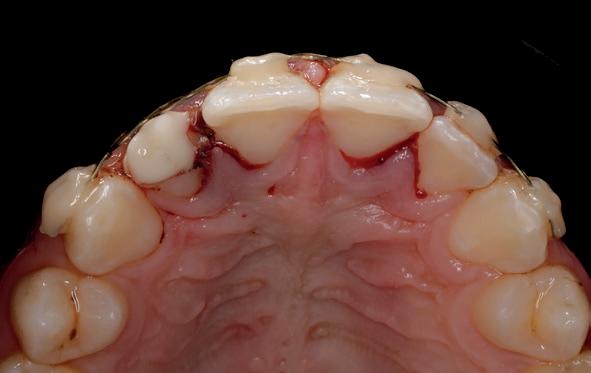

Na zes weken zagen wij hem voor het eerst bij ons in de praktijk voor consult. Hij was klachtenvrij en kon redelijk kauwen met zijn tanden (afbeelding 1-6).

We zijn begonnen met de 13 en hebben een week later de 12 en de 11 behandeld. Bij de 13 kon een volledig necrotische pulpa worden geëxtirpeerd (afbeelding 7). Aangezien we aan de vitaliteit van de 12 en 11 twijfelden, hebben we eerst een proefboring uitgevoerd en beide elementen bleken volledig necrotisch.

De kanalen zijn ultrasoon gespoeld met 2% NaOCl en EDTA onder isolatie van rubberdam. Het kanaal van de 13 is gevuld met MTA (afbeelding 8), omdat er sprake was van een niet-afgevormde radix. Dit is afgedekt met een laagje Vitrebond. In de 12 en 11 hebben we guttapercha en AH26 aangebracht via een hybride vultechniek (afbeelding 9).

Er is een plastische opbouw vervaardigd van het composiet opbouwmateriaal Clearfil core, dat diep is verankerd in het kanaal. Er is een definitieve restauratie vervaardigd van composietmateriaal Filtek Z250 kleur A3 (afbeelding 10 en 11). De behandeling is technisch goed verlopen. Echter, we hebben hem en zijn moeder uitgelegd dat de prognose

van de 13 voor de lange termijn dubieus was.